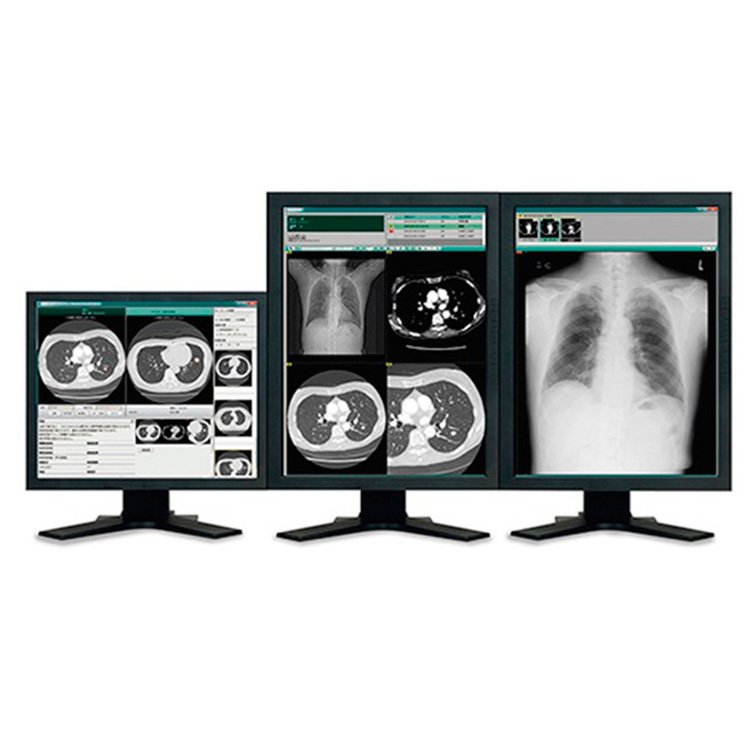

Estación de diagnóstico ideal para el mamógrafo AMULET Innovality incorporando las últimas tecnologías propias de FUJIFILM. La estación de trabajo muestra rápidamente los estudios mamográficos incluso cuando estos poseen una gran cantidad de información, como estudios de tomosíntesis y biopsia.

- SYNAPSE PACS

- SYNAPSE RIS

- SYNAPSE VNA

- SYNAPSE MOBILITY